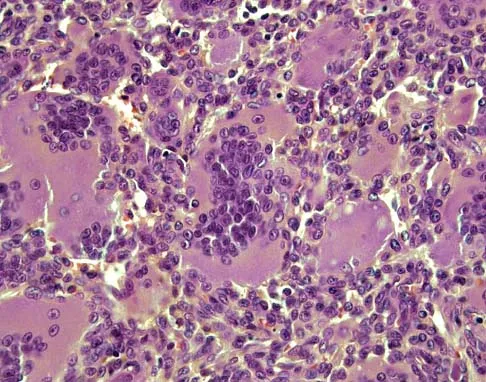

Figures 27a through 27c show the AP radiograph, MRI scan, and biopsy specimen of an otherwise healthy man who has a painful wrist. Serum chemistry studies are normal. What is the most likely diagnosis?